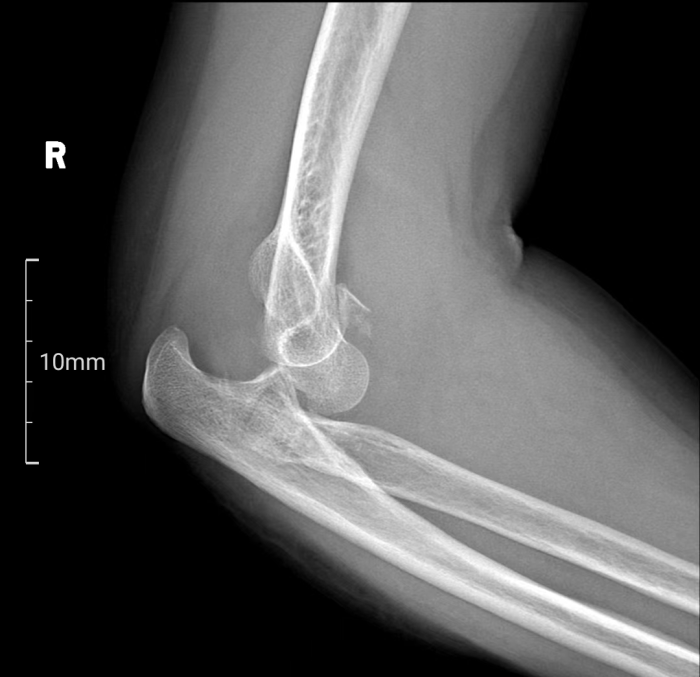

术前二维影像

肘关节恐怖三联征,作为一种复杂的肘关节骨折脱位类型,同时涉及肘关节后脱位、桡骨头骨折及尺骨冠突骨折三种损伤,其治疗难度极高。面对这一挑战,南溪山医院创伤骨科与手外科张立主任团队凭借其丰富的临床经验和前瞻性的技术视野,决定采用先进的3D打印技术为患者提供个性化治疗方案。

患者梁女士因不慎跌倒导致右肘关节疼痛并活动受限,经X线检查确诊为肘关节恐怖三联征。面对这一复杂病情,张立主任迅速组织科室医生及3D打印中心技术人员进行病例讨论,并决定采用3D打印桡骨小头置换术进行治疗。